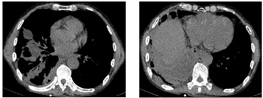

胸部CT(图2、图3):右肺下叶团块状影伴液化坏死,考虑感染(肺脓肿可能),不除外肿瘤;双肺下叶散在感染灶;右侧胸膜增厚,右侧胸腔积液,部分包裹;纵隔淋巴结肿大。床旁心电图:窦性心律,正常心电图。红细胞沉降率82 mm/h;血常规:白细胞计数22.66×109/L,中性粒细胞绝对值19.66×109/L,淋巴细胞绝对值0.72×109/L,嗜酸细胞绝对值0×109/L,血红蛋白121 g/L,中性粒细胞百分率86.8%;C反应蛋白343.78 mg/L;肝功能:谷丙转氨酶19 U/L,谷草转氨酶36 U/L,白蛋白38.7 g/L,前白蛋白93 mg/L,间接胆红素18.6 umol/L,直接胆红素13.7 umol/L,总胆红素32.3 umol/L;肾功能正常;血钠133.3 mmol/L;随机血糖7.87 mmol/L;凝血功能:纤维蛋白原降解产物5.5 μg/ml,血浆纤维蛋白原8.8 g/L,D-二聚体0.97 mg/L;血气分析(吸氧2 L/min):酸碱度7.47,氧分压81 mmHg,二氧化碳分压39.3 mmHg,剩余碱4.1 mmol/L,氧饱和度96.6%;降钙素原2.65 ng/ml;心肌梗死标志物、N-末端脑钠肽前体、肺肿瘤标志物、感染性疾病筛查未见异常;2019新型冠状病毒核酸阴性;常见呼吸道病原体抗体阴性;G试验阴性;痰涂片查结核、真菌阴性;痰、血培养阴性。